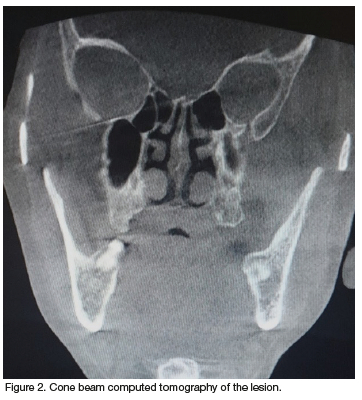

Clinical examination revealed a solid, exophytic and non-tender horn-like lesion; grey- white- black in appearance with brown vertical striae. The colour and texture skin at the base of the lesion was similar to the peripheral skin. Furthermore, the lesion was 6cm in length (Figure 1). There was no regional lymphadenopathy. An ultrasound and radiographic examination did not reveal any abnormalities associated with the lesion (Figure 2). Interestingly, the ultrasound showed that the base of the lesion was avascular. Based on the clinical and radiographic features a provisional diagnosis of a cornu cutaneum was made. The pre-operative investigations included full blood count, urea and electrolytes and the findings were unremarkable.